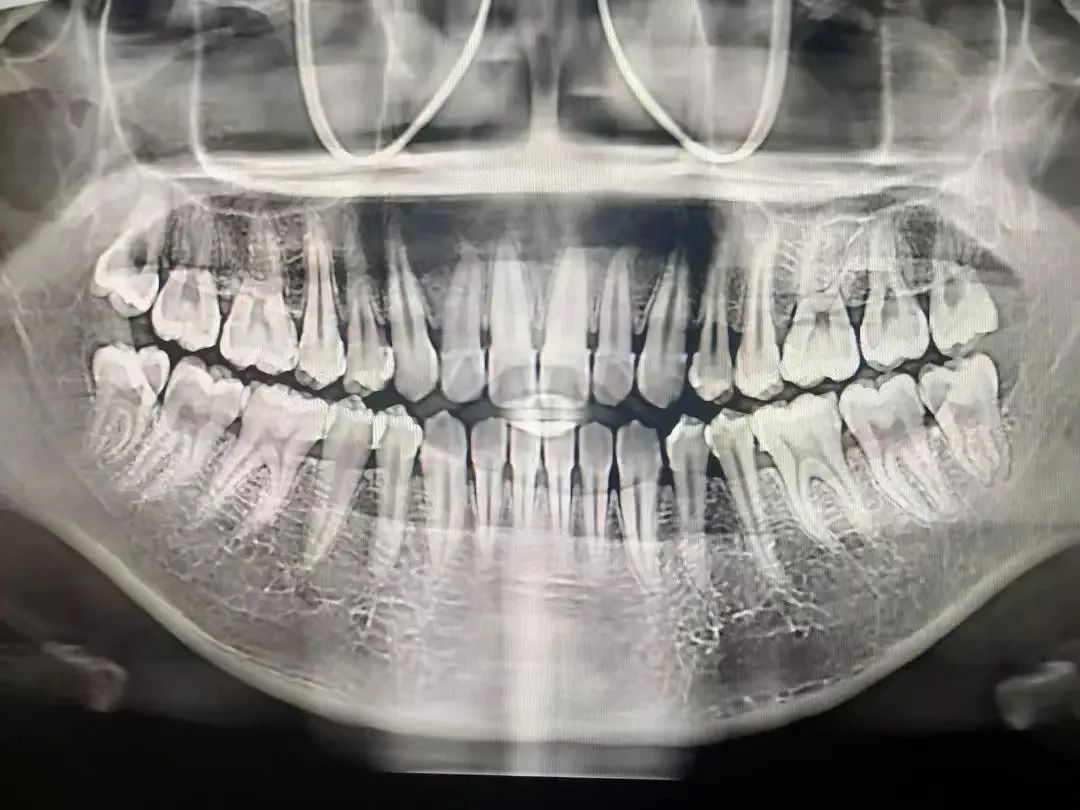

图片

一些人不愿意照牙片,认为医生看看牙齿情况就可以了。

要知道医生的眼睛不是透视镜,牙齿好比大树,树根扎在土壤里,而我们的牙根也埋在牙槽骨里,牙根的状态、里面的神经肉眼都是看不到的。只有通过牙片,牙医才可以确切了解龋坏的范围、牙痛是由牙髓炎还是根尖炎或是牙周炎引起、种植牙需要的骨量等

专家建议

相信医生,拍牙片可以为你保留最原始资料,让医生准确判断你的病情,更好地为你诊疗。